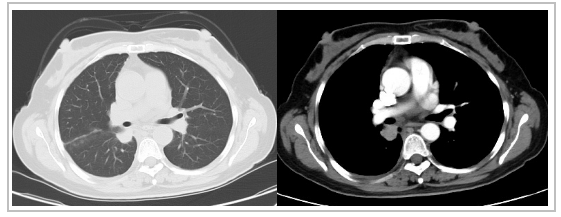

病例介紹:患者,女,51歲。因咳嗽、咳痰伴胸背部疼痛3個月就診。2020年7月頸胸上腹CT檢查發現.右肺下葉近肺門處佔位,考慮肺癌可能;右側葉間胸膜結節狀增厚,考慮轉移。其餘檢查無異常發現。透過右肺佔位EBUS活檢,病理診斷為非小細胞癌,傾向腺癌,ARMS-PCR法肺癌基因檢測顯示EGFR-21 L858R突變。初步診斷為右肺癌並右側胸膜轉移(腺癌,cT1aN0M1a,ⅣA期;EGFR-21 L858R突變)

治療過程:一線給以每天口服250mg吉非替尼,同時聯合貝伐珠單抗,每次靜脈注射500mg,21天重複1次。治療2週期後療效評估PR,維持至今,PFS>15個月,不良反應輕微。